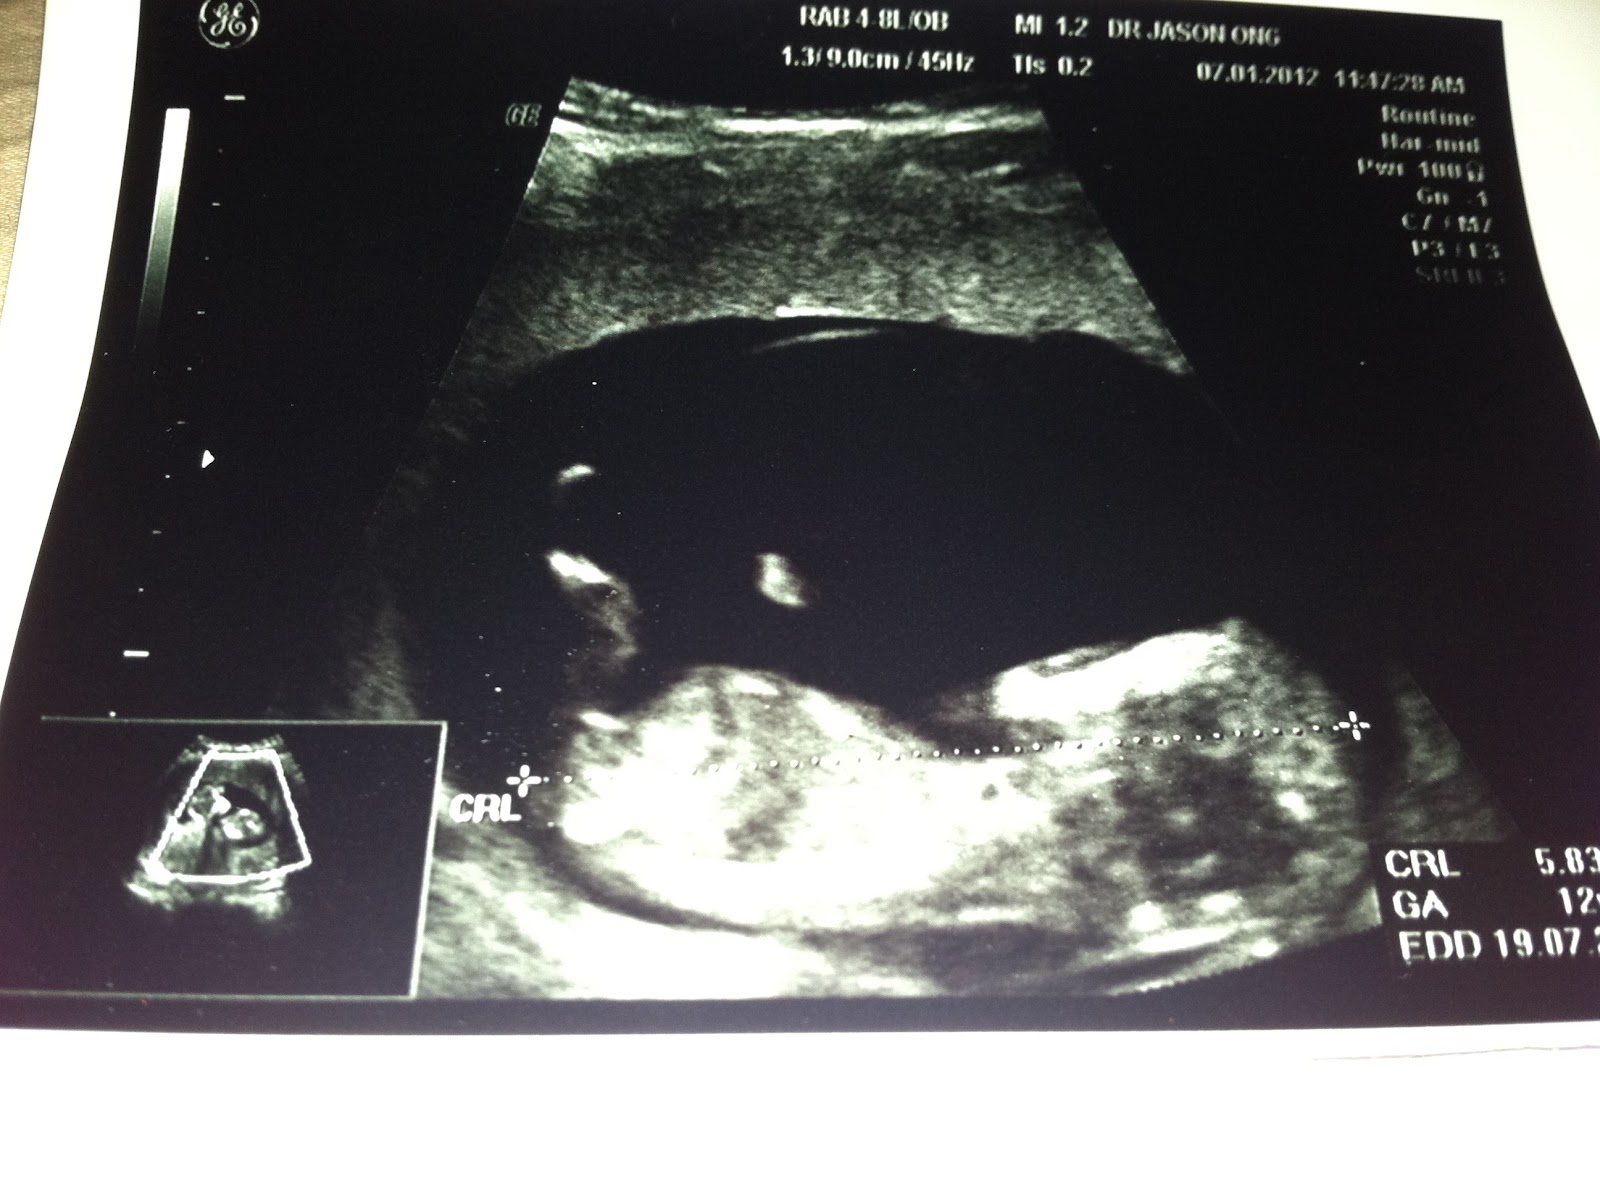

我的 bb Ultrasound和怀孕征兆。。(更新:16 周了 - 8页 177楼)

hahahha~很可爱的宝宝~我应该和你一样吧。我1月3号去复诊,也12个星期~感觉很奇妙的~希望我们的宝宝都健康出生~~~~我不敢喝吃冷的,因为听说不好,可是酸的东西我一定吃~因为就喜欢吃吧~还有,我不爱吃鸡肉= =味道也要比较重,最好是韩国菜之类的~~~哈哈哈~~~ |

哗 你的宝宝照到很清楚了,我的每次都很不清楚 |

看到mm的bb照...超感动的. 我也刚在昨天照了ultrasound..10星期.. 3.16cm 看到小手和小脚了.  |

今天的产检跟往常一样,就是照b超,主要是看宝宝有没有唐氏,还有看看性别(如果宝宝合作的话)。 12周的宝 ...